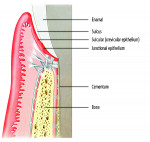

Firstly, understand that the requirements of the implant restoration are completely different from the natural tooth. With a natural tooth, the attachment of the soft tissues produce a tight, distinct seal through cementum on the tooth root and mineralized Sharpey’s fiber insertion. For an implant, the soft tissues adhere to an implant surface via a fragile hemidesmosomal attachment—the weakest cell attachment known in the human body. The implant attachment can be readily disrupted by cement flow being pushed into the tissues as the crown seats8 (Figure 1 and Figure 2).